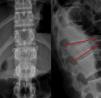

Acuñamiento lateral4Se mide en un plano coronal. Es un ángulo formado por las proyecciones de los platillos superior e inferior de la vértebra fracturada. Se considera inestable cuando el ángulo supera los 20° (fig. 2, izquierda)

Índice de Beck5Se mide en plano sagital y define el acuñamiento vertebral de forma porcentual midiendo la diferencia de altura en el muro anterior respecto del posterior en la vértebra fracturada. Determinan inestabilidad valores superiores al 50% (fig. 2, derecha)